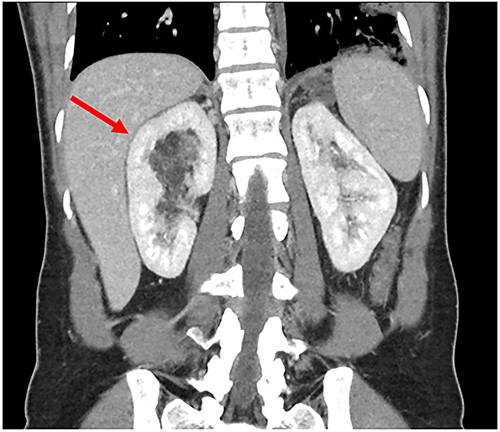

A 34-year-old female presented with acute onset left-sided chest pain and was found to have an occlusive PE in the left lower lobe. She was initiated on a heparin infusion. Imaging partially revealed a mixed-density lesion in the right kidney, which was further evaluated with a dedicated computed tomography (CT) scan and magnetic resonance imaging (MRI). This demonstrated concern for an AML involving the upper pole of the right kidney, with extension of tumor thrombus into the right renal vein and IVC (Figs 1 and 2). At this point, surgical oncology and cardiothoracic surgery (CTS) were involved to discuss resection. An echocardiogram confirmed that the tumor thrombus did not extend into the cavoatrial junction. MRI of the brain was ordered to rule out a rare presentation of tuberous sclerosis. Percutaneous renal biopsy demonstrated AML with epithelioid features. She was transitioned to therapeutic Lovenox and discharged with plans for surgical resection within the following week.

Preoperative MRI with tumor thrombus extension into right renal vein.